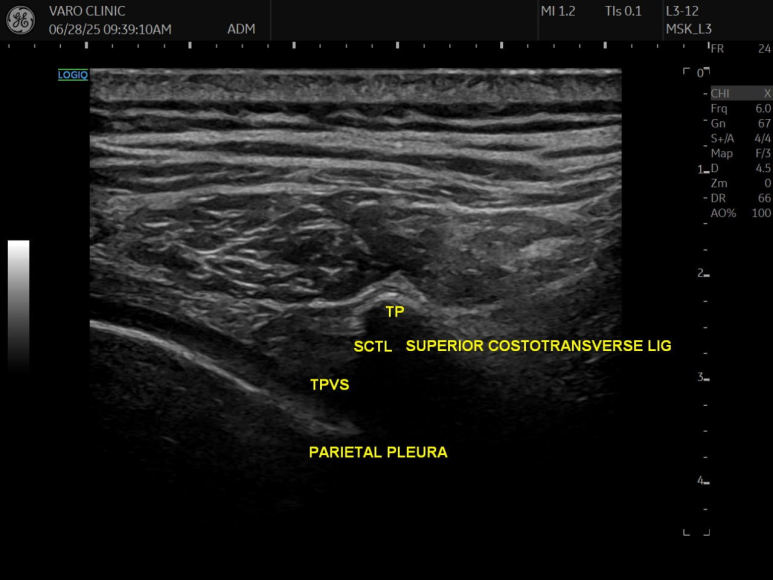

위갈비가로돌기 인대 (SCTL)

superior costotransverse ligament

이 '척추옆 공간'의 뒤쪽에는

'위갈비가로돌기 인대(SCTL)'라는

아주 튼튼한 인대성 막이 존재합니다.

경혈 초음파를 통해

실시간으로 신경과 혈관,

그리고 문제의 '위갈비가로돌기인대'를

눈으로 직접 보면서 시술할 수 있습니다.

초음파 화면을 눈으로 보면서

안전하고 정밀하게 시술할 수 있습니다.